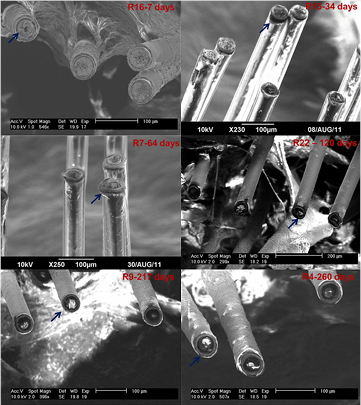

Unfortunately, in chronic applications, corrosion is again a limiting factor for their success as implants. Prasad et al [54] note that while W microwires are able to initially provide stable recordings, they fail to do so for years, reporting roughening of the surfaces of their 50 µm diameter microelectrodes two h after implantation, recession and cavitation of surfaces after two weeks to 16 d, and eventual cracking, pitting, hole-formation, and deep recession of the electrodes into the insulation in months following (figure 6). Williams [85] reports W microwire electrodes of 35 µm diameter (unsharpened) having viability of continuous recordings from guinea pig tests of only five weeks or less. Sanchez et al [87] reportes corrosion of W microwires after four weeks of in vivo implantation. Others report similar degradation of recording surfaces of W microwires [87].

Figure 6. Post-explantation SEM images of 16-channel tungsten microwire arrays with 50 µm diameter electrodes coated with 10 µm thick polyimide insulation. The images depict the progression of electrode recording site corrosion and deterioration for increasing implant durations in different rats labelled by 'R' (R16: 7 d; R15: 34 d; R7: 64 d; R22: 122 d; R9: 217 d; R4: 260 d). The arrows (original authors' addition) indicate examples of polyimide delamination and electrode recording site corrosion for individual electrodes [54].

Standard image High-resolution imageA very thorough analysis of this corrosion phenomenon was performed by Patrick et al [13] on commercial 50 µm diameter W microwires (California Fine Wire) encased in epoxy (Epotek 302-3M). Reported bench-top corrosion rates were 300–700 µm yr−1 for pure W in 0.9% PBS, and 10 000–20 000 µm yr−1 for Au-plated W (gold deposited circumferentially) in 0.9% PBS + 30 mM H2O2 (the latter to simulate the highly oxidative environment of post-implantation inflammation). Assuming 100% W, ideal cylindrical geometry, full density, and ρw = 19.25 g cm−3, this corresponds to 0.45–1.1 µg yr−1 and 15–30 µg yr−1, respectively. No data on pure W in PBS/H2O2 was offered.

Simultaneous in vivo studies in adult male Sprague–Dawley rats implanted cranially with Au-plated W reported corrosion rates of 100 µm yr−1 (0.151 µg yr−1) with the difference hypothesised to be due to the formation of an oxygen-blocking biofilm [13].

From purely visual analysis, in the PBS-only samples, the electrode surfaces polished to 1 µm smoothness displayed roughening after 1 d, pitting after 2 d, and full recession from the initial surface after 6 d to a depth of >4 µm, similar to the reports by Prasad. In the in vivo studies, the W receded within its insulation 24 ± 8 µm after 87 d of implantation (figure 7). Similar results were reported by others (figure 8). No oxide layer was present in either case, contradicting claims of oxide passivation due to localised acidosis.